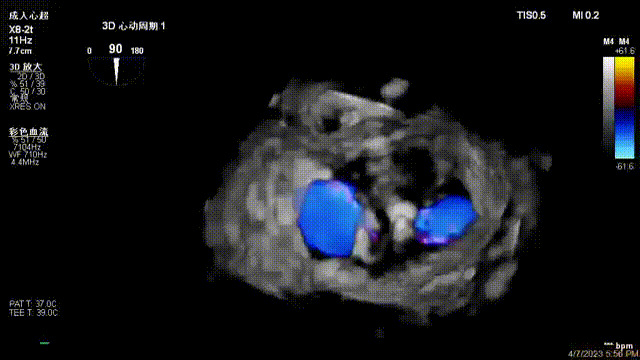

術(shù)后超聲顯示二尖瓣反流消失,瓣膜夾穩(wěn)定

出院前隨訪超聲